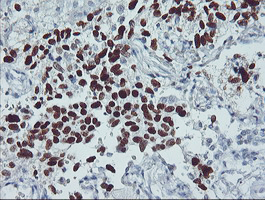

TP53

IHC of paraffin-embedded Carcinoma of Human lung tissue using anti-TP53 mouse monoclonal antibody.